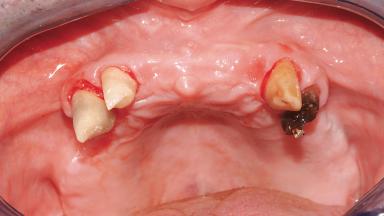

Immediate Loading of Six Implants in the Maxilla and Final Restoration with a Full-Arch Gold/Ceramic FDP Involving the Concept of Tilted Implants

A 61-year-old male patient with a failing fixed maxillary rehabilitation and a fixed mandibular rehabilitation requested a new fixed maxillary rehabilitation. The patient was wearing a temporary metal-reinforced maxillary bridge inserted two years before the consultation. He reported that his previous dentist did not want to insert a definitive framework because he considered the residual teeth to have a negative prognosis. The patient reported a history of recurrent caries and endodontic complications as the main reason for the previous extractions. The anamnesis was negative for periodontal disease and bruxism. The patient’s chief compliant was the mobility of his maxillary prosthesis, which needed to be re-cemented frequently, and discomfort during chewing.Moreover, the patient was not satisfied with the esthetic appearance of his maxillary teeth, which he found too long. The patient asked for a stable and comfortable fixed maxillary rehabilitation and firmly rejected any removable solution.

Case Type Edentulous Maxilla

Jaw Maxilla

Area Full-Arch

# of Teeth All